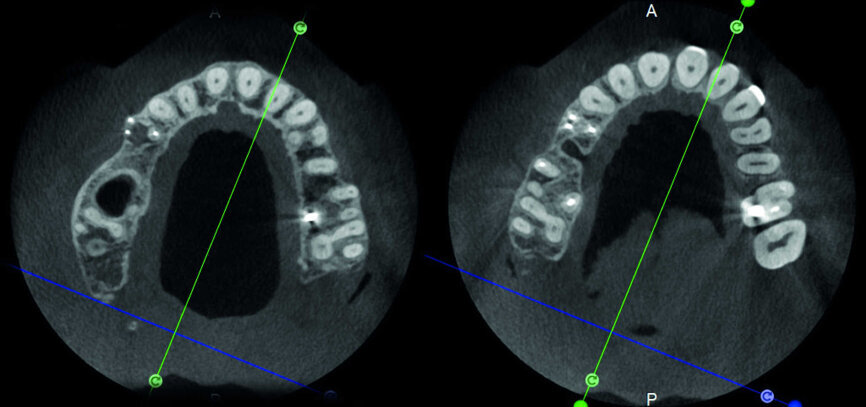

Le cas avec lequel je souhaite commencer mon exposé clinique est un exemple parfait de la difficulté à définir l’origine des symptômes d’un patient, par l’examen d’une simple radiographie intraorale. Non seulement l’examen 2D ne permet pas d’établir avec certitude la présence d’une lésion, mais surtout, il est impossible d’en déterminer la taille, la morphologie et le type. Au contraire, une analyse de l’imagerie 3D offre une image claire de la situation clinique. Chez ce patient, les coupes coronales et sagittales révèlent la présence d’une importante lésion s’étendant de l’apex de la racine mésiale de cette molaire jusqu’à la zone de furcation, tandis que les coupes axiales nous permettent d’analyser précisément l’anatomie endodontique et, en particulier, la forme de la racine mésiale, qui apparaît fusionnée avec la racine palatine. Un panorama complet du cas peut donc guider le processus de décision et orienter le plan de traitement vers une modalité bien précise de traitement (Figs. 1–4).